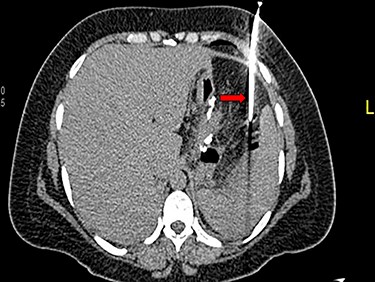

A 36-year-old obese female patient underwent a sleeve gastrectomy abroad. Eleven days after surgery, she presented with an abdominal pain. Abdominal computer tomography (CT) revealed several fluid-air collections (3 abscesses) around the upper greater gastric curve (3.5 × 3.2 cm), lesser sac (7 × 3.3 cm) as well as anterior to the spleen (7 × 3.3 cm). By that time, there was also left pleural effusion and atelectasis of the left lower lung lobe. On the next day, CT-guided aspiration was done (Fig. 1) and a pigtail catheter was inserted to drain the abscesses. On the following day, water-soluble oral contrast displayed an active contrast leak along the proximal sleeve gastrectomy (Fig. 2). On the same day, covered esophageal stent was placed endoscopically. The patient was discharged home and was scheduled for stent removal after 2 weeks. However, after 2 days, the patient presented again with an abdominal pain. The plain x-ray showed slippage of the stent distally. Upper GI endoscopy was done, and the esophageal stent was removed. One day later, the patient condition deteriorated with a massive upper GI bleeding. A CT angiography showed no extravasation and the source of bleeding was not identified during endoscopy due to massive bleeding. An immediately performed angiogram revealed an AEF (Fig. 3). The interventional radiologist achieved transient cessation of the bleeding through embolization of the fistula with interlock coils (Fig. 3). An aortogram showed continuous extravasation of contrast through the fistula, and therefore, endovascular intervention was performed with implantation of 22 mm × 112 mm aortic stent (TEVAR using Valiant covered stent - Medtronic company, USA). One week after TEVAR, another long esophageal stent was positioned (from lower esophagus to the stomach). Two weeks later, a barium swallow proved no evidence of contrast leak. Then, the esophageal stent was removed, and the patient was discharged home. There was a plan for definitive reconstruction procedure, including removal of the endovascular stent and use of reconstructed pericardial bovine graft, however, the patient declined. About 10 months later, she presented with another attack of massive hematemesis, with a drop of hemoglobin to 8 g/dl and a blood pressure of 66/44 mmHg requiring a rapid sequence induction and infusion of packed red blood cells. An immediate abdominal CT showed evidence of peri-stent infection with no contrast extravasation. Upper GI endoscopy showed an evidence of an ischemic ulcer above the Z-line with granulation tissue at the ulcer edge and erosion of the endovascular stent into the lower esophagus. The patient had a positron emission tomography (PET) scan and diagnosed with mediastinitis due to aortic stent infection and septic shock (Fig. 4). Surgical intervention was offered but the patient declined. Treatment with broad spectrum antibiotics and blood transfusion were administrated as required. Around 5 weeks later, the patient developed massive upper GI bleeding requiring intubation and surgical intervention (distal esophagectomy with removal of the endovascular stent and resection and replacement of the AEF site with reconstructed tube using 14 × 9 cm bovine pericardial graft through left thoraco-abdominal incision utilizing left cardiopulmonary bypass and distal perfusion through left femoral artery (Fig. 5). Closure of the stomach with gastrostomy tube insertion for feeding had been performed. One and half year later, reconstruction surgery of the esophagus with colonic interposition was done. After 3-year follow-up, the patient was doing well with no complication.